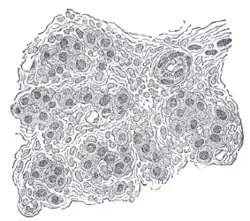

![]() Seção de parte do corpo carotídeo humano. Altamente ampliado. Numerosos vasos sanguíneos são vistos na seção entre as células. | |